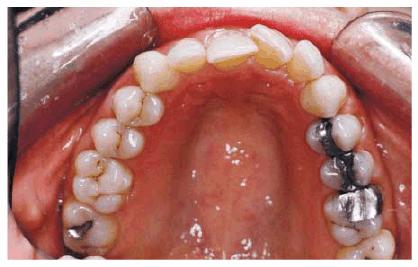

PROBLEM: This 30-year-old horse trainer had extremely large central

incisors (Figure 24-3A). In addition, the mandibular

centrals were crowded and rotated lingually (see Figures 24-3A, and 24-3B

Figure 24-3A: This 30-year-old woman had extremely large central incisors with overlapping maxillary and mandibular teeth.

Figure 24-3B: An occlusal view showing the overlapping central incisors.

TREATMENT: Although the patient was informed about the advantage of

orthodontics as the ideal treatment, she nevertheless chose an immediate

correction in the form of esthetic contouring and esthetic resin bonding. The

central incisors were first contoured on the study cast to approximate the

desired tooth size. Esthetic contouring was accomplished in both the maxillary

(Figure 24-3C) and mandibular arches (Figure 24-3D). Next, the lateral incisors were

bonded labially to round out a more symmetric arch (Figures 24-3E, and 24-3F